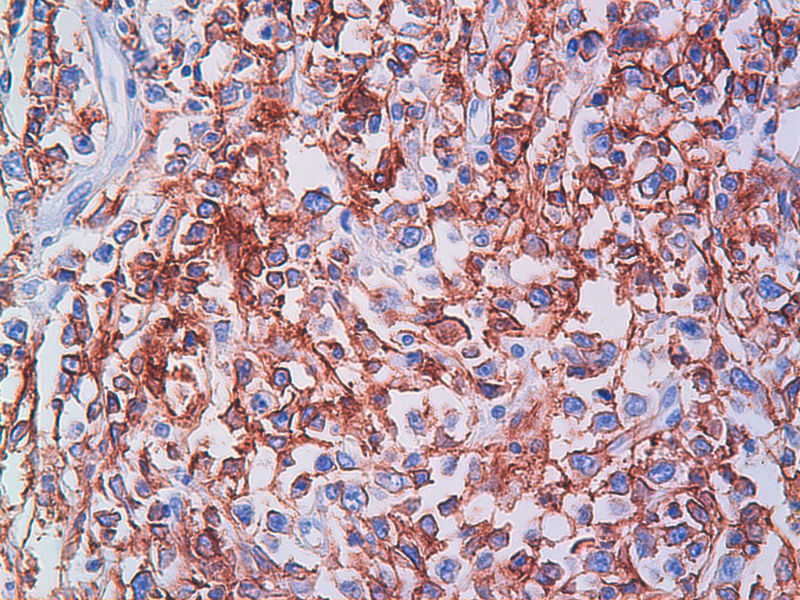

免疫组化染色:CA125(-),PLAP(-),NSE灶状阳性,Vimentin(+),a-inhibin(-),CK7(-),CK20(-),CD15(-),PSA(-),S100(-),MyoD1(-),CD38(-),CD56(-),HMB45(-),CK8(-),NF(-),CGA(-),syn(+),MPO散在(+)可能是炎细胞吧,LCA(+),CD133(+).

今天又做了免疫组化,请大家帮看看。CD10(-),CD138(-),CDX2(-),CD3(-),CyclinD1(-),CD2(-),CD117(-),CD7(-),CD30(-),CD23(-);CD20强(+),BCL-2,Bcl-6,EMA,PAX-5,MUM-1,CD5,ALK,CD68都是散在阳性,大家帮确定一下是否阳性。B细胞淋巴瘤可以确定了,不知是哪种类型的?